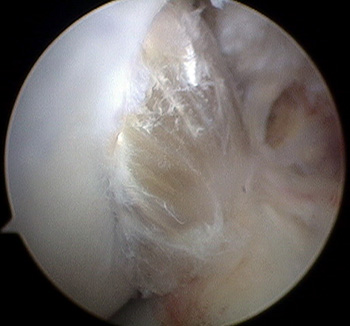

maestu1_fig7

Figura 7: vista artroscópica desde portal anterolateral de fijación femoral en simple banda en una rodilla izquierda.